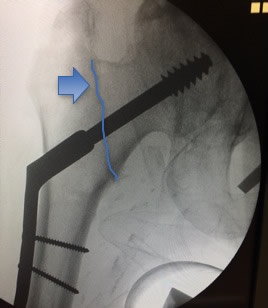

Fig. 2 - Fratura Trocantérica